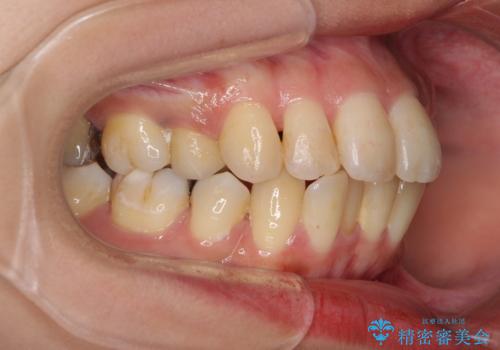

後戻りで突出した前歯をインビザラインで解消

- 抜歯矯正の後戻りで前歯が突出してきていることを気にして来院された患者様です。

口元の突出感を改善するにあたり、抜歯矯正は行うことができないため、奥歯の後方移動とIPR(歯と歯の間を削る)により達成することとしました。

再度後戻りしたときに対応しやすいよう、インビザラインにて矯正治療を行うこととしました。

舌の突出癖がなかなか改善できず、IPRによる前歯の隙間が閉じきらずに、予定よりも長い治療期間となりました。